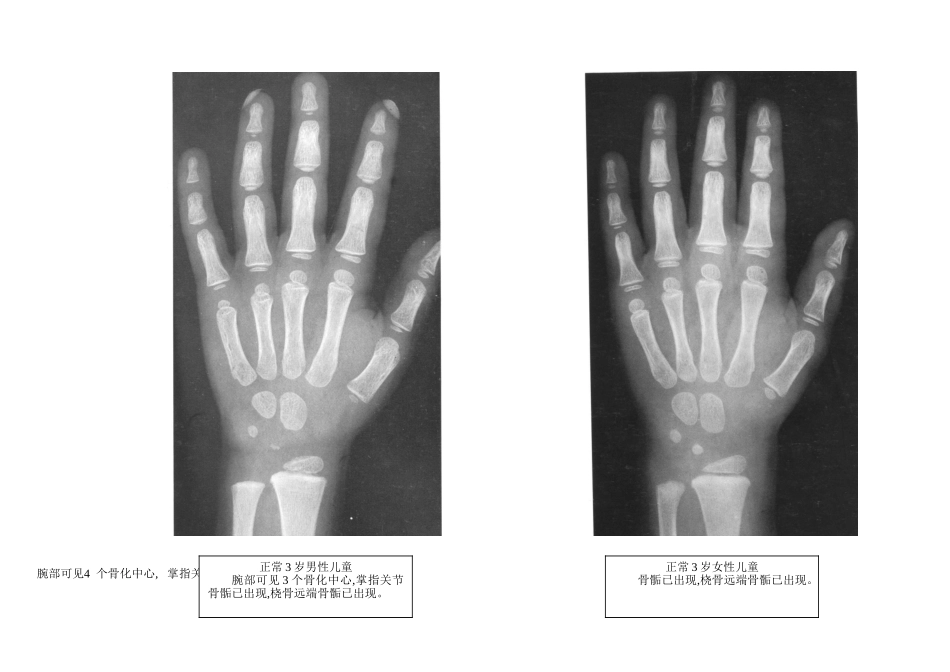

正常骨龄图谱骨龄得估量在骨得发育过程中,每一个骨得骺软骨内继发骨化中心出现时得年龄与骺与干骺端得完全结合,即骺线完全消逝得年龄,称为骨龄(bone age)。根据正常男女各骨化中心得出现与骺与干骺端结合时期得差别范围可制定一个正常骨龄范围。健康儿童得骨发育速度有个体差异,同一个体两侧肢体得骨化中心得出现亦不完全一致,但骺愈合得时间却绝大多数就是两侧对称得。一般而言男性骨化中心出现时间与干骺愈合时间皆晚于女性 1~2 岁。 0 正常 1 岁男性儿童腕部可见 2 个骨化中心,掌指关节骨骺尚未出现。正常 1 岁女性儿童腕部可见 2 个骨化中心,掌指关节骨骺已部分出现,桡骨远端骨骺已出现。 正常 2 岁男性儿童腕部可见 2 个骨化中心,掌指关节骨骺已部分出现,桡骨远端骨骺已出现。正常 2 岁女性儿童腕部可见 3 个骨化中心,掌指关节骨骺已全部出现,桡骨远端骨骺已出现。 腕部可见4 个骨化中心, 掌指关节正常 3 岁男性儿童腕部可见 3 个骨化中心,掌指关节骨骺已出现,桡骨远端骨骺已出现。正常 3 岁女性儿童骨骺已出现,桡骨远端骨骺已出现。 正常 4 岁男性儿童腕部可见 5 个骨化中心,掌指关节骨骺已出现,桡骨远端骨骺已出现。正常 4 岁女性儿童腕部可见 7 个骨化中心,掌指关节骨骺已出现,桡骨远端骨骺已出现。 正常 5 岁男性儿童腕部可见 5 个骨化中心,掌指关节骨骺已出现,桡骨远端骨骺已出现。正常 5 岁女性儿童腕部可见 7 个骨化中心,掌指关节骨骺已出现,桡骨远端骨骺已出现。 正常 6 岁男性儿童腕部可见 7 个骨化中心,掌指关节骨骺已出现,尺、桡骨远端骨骺已出现。正常 6 岁女性儿童腕部可见 7 个骨化中心,掌指关节骨骺已出现,尺、桡骨远端骨骺已出现。 正常 7 岁男性儿童腕部可见 7 个骨化中心,掌指关节骨骺已出现,尺、桡骨远端骨骺已出现。正常 7 岁女性儿童腕部可见 7 个骨化中心,掌指关节骨骺已出现,尺、桡骨远端骨骺已出现。 正常 8 岁男性儿童腕部可见 7 个骨化中心,掌指关节骨骺已出现,尺、桡骨远端骨骺已出现。正常 8 岁女性儿童腕部可见 7~8 个骨化中心,掌指关节骨骺已出现,尺、桡骨远端骨骺已出现。 正常 9 岁男性儿童腕部可见 7~8 个骨化中心,掌指关节骨骺已出现,尺、桡骨远端骨骺已出现。正常 9 岁女性儿童腕部可见 8 个骨化中心,掌指关节骨骺已出现,尺、桡骨远端骨骺已出现。 正常 10 岁男性儿童腕部可见 7~8 个骨化中心,掌指关节骨...